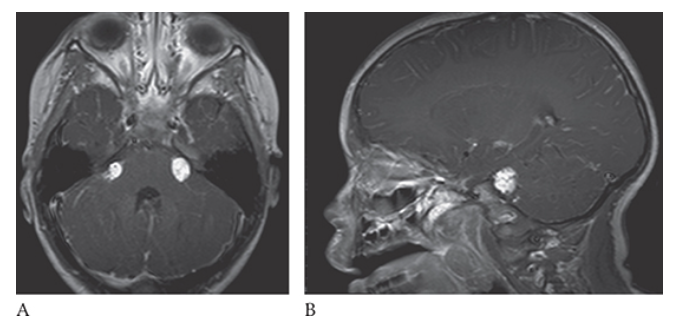

What is A

Lipoma. T1W axial and sagittal

What is B

Lipoma. T1W axial images show small high-signal-intensity masses in both cerebellopontine angles.